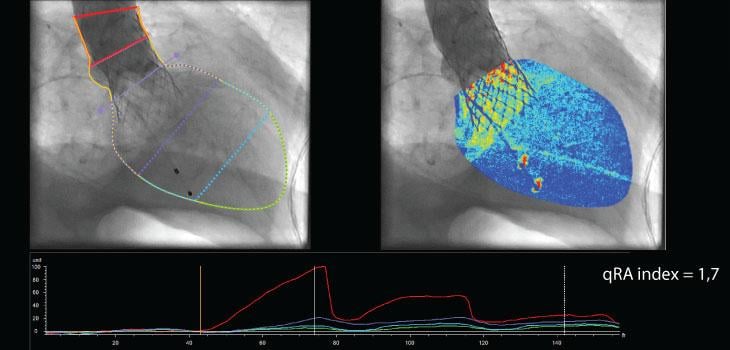

Image courtesy of Pie Medical Imaging

The qRA workflow provides objective and reproducible quantification of aortic regurgitation by using density of contrast in the aortic root and ventricle based on X-ray aortogram images. Visual determination is inaccurate and can lead to underestimation of regurgitation. The qRA workflow is developed to quantify the regurgitation directly after percutaneous valve replacement. In addition to the qRA workflow, CAAS A-Valve assists to define the optimal C-arm projection to place the prosthetic valve.